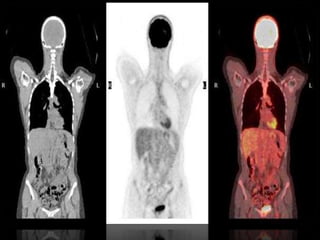

• PET-CT: radionuclide imaging devices

• The resulting images display the

functional data obtained from the

radionuclide distribution (usually in

color) overlaid on the anatomical

information from CT (usually in grey

scale)